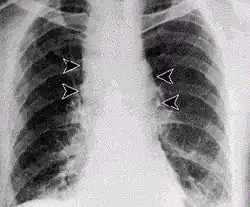

Lungenmilzbrand im Röntgenbild

Durch Einatmen von sporenhaltigem Staub entsteht der Lungenmilzbrand, auch Hadernkrankheit genannt.[10] Für einen Krankheitsausbruch (apparente Infektion) müssen ca. 3000–9000 Milzbrandsporen mit der Atemluft inhaliert werden, die an Tierhäuten oder Tierhaaren haften und noch nach Jahren ansteckend sind. Die Inkubationszeit beträgt einige Tage bis zu mehreren Wochen. Die Krankheit beginnt unspezifisch und grippeähnlich mit Husten, es folgen hohes Fieber, Schüttelfrost und Atemnot. Das ausgehustete Sekret ist hochinfektiös. Auch mit sofortiger antibiotischer Therapie (Ciprofloxacin, Doxycyclin, Penicillin G bzw. V) ist die Letalität (Sterbensrate) an Lungenmilzbrand sehr hoch, da mit dem Auftreten der Symptome eine massive Freisetzung der Milzbrandtoxine bereits stattgefunden hat. Der Tod tritt meistens innerhalb von drei bis sechs Tagen unter dem Bild eines septischen Schocks ein.